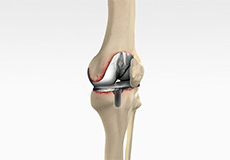

ACL Preserving Total Knee Replacement

ACL preserving total knee replacement is an advanced surgery performed to replace a damaged knee joint with a prosthesis while preserving the anterior cruciate ligament (ACL). The ACL is a very important ligament that runs diagonally across the front of the knee and provides rotational knee stability.